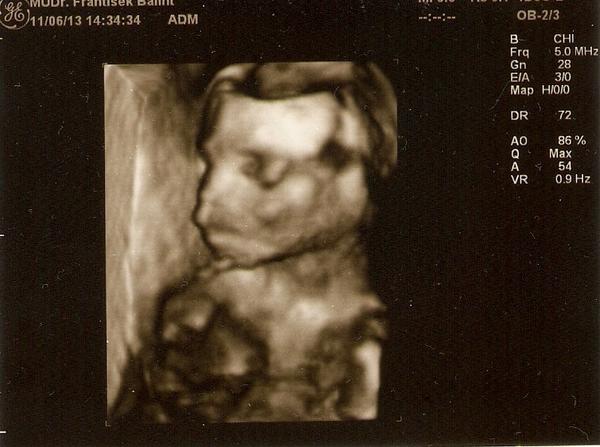

ahojte baby, morfo ultrazvuk máme za sebou, všetko je vraj ok a moje tušenie sa potvrdilo "čakáme babu" 🙂 Dcéra sa teší, lebo ona od začiatku chcela iba sestru, už len jej vybrať meno 🙂

tak dnesne morfo... male je v poriadku...4 ruky a 2 nohy 🙂 ...krasne mi lekar vsetko ukazal ...320g... zase ako pri prvom ma "vecsie" hodnoty, tak uz sa v duchu pripravujem na dalsieho valibuka a dalsiu sekciu, ale ma potesil, ze dnes sa da zvladnut aj 5 sekcii, ze ma jednu mamicku so 4 sekciami a caka dalsie. Uplne iny postoj ako tu citavam od mamiciek, ze maju lekari.